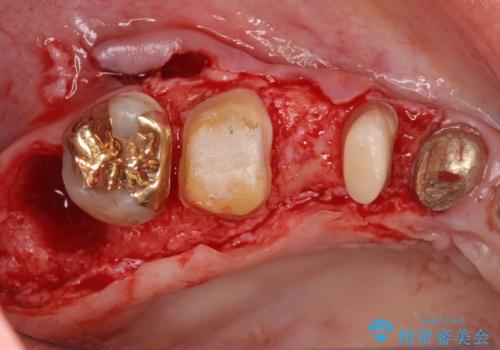

歯周ポケットの除去を併用したセラミック治療

適合や審美性に優れるセラミック治療を行う前に、歯周病の問題を歯周外科を行うことで解決し将来的に不安のないような口腔内環境を整備していきます。

治療前に4-5mm程度あった歯周ポケットは全て2mm以内となり、非常に清掃性が高く、歯周病の再発しずらい環境に整えた上でのセラミック治療を実践することができました。